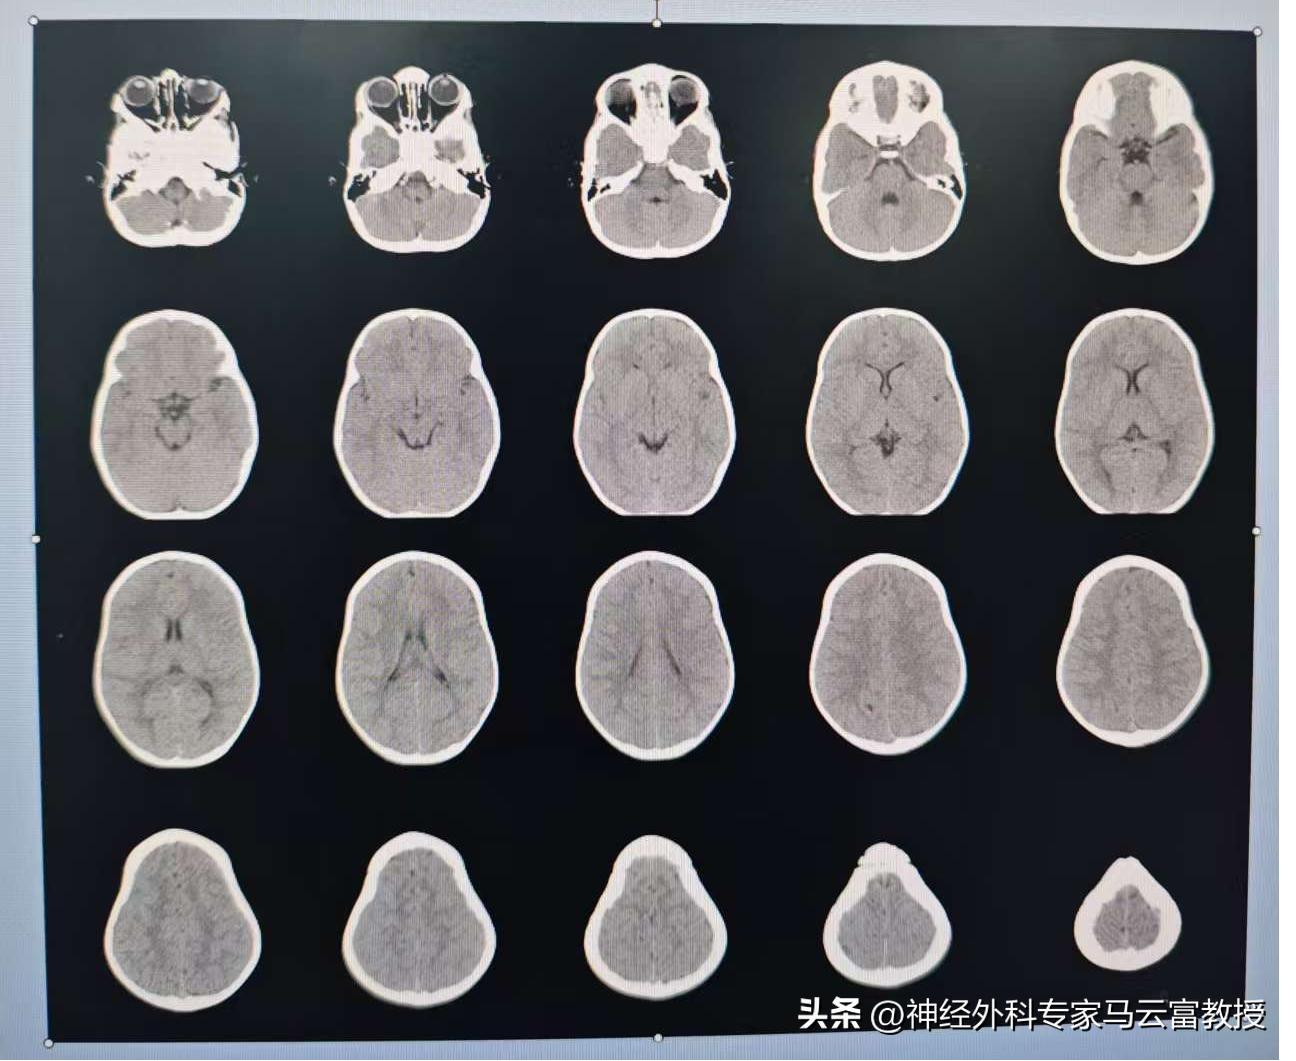

接診後,神經外科團隊迅速啓動 “綠色通道”,爲患兒開展全方位診療評估。通過高分辨率術前 CT 掃描與三維重建技術,團隊清晰還原了患兒顱骨閉合的具體位置、程度及腦組織受壓情況,精準測算出顱腔容積缺口。

手術當日,在全麻團隊的密切配合下,馬雲富教授憑藉毫米級的操作精度,逐步完成顱骨截骨、畸形矯正、固定等關鍵步驟。整個手術歷時 4 小時,出血量控制在極低水平,完美實現了術前預設的矯治目標。術後,患兒被轉入小兒 ICU 進行密切監護,在醫護團隊的精心照料下,次日便順利脫離呼吸機,意識清晰、反應良好。一週後複查顯示,患兒顱內壓恢復正常,頭顱形態較術前有顯著改善;出院時,孩子已能正常進食、活潑哭鬧,曾經異常的頭顱輪廓正逐步向正常形態趨近。